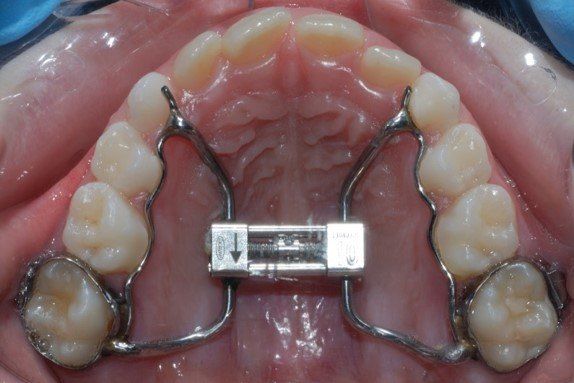

TIPOS DE APARATOS